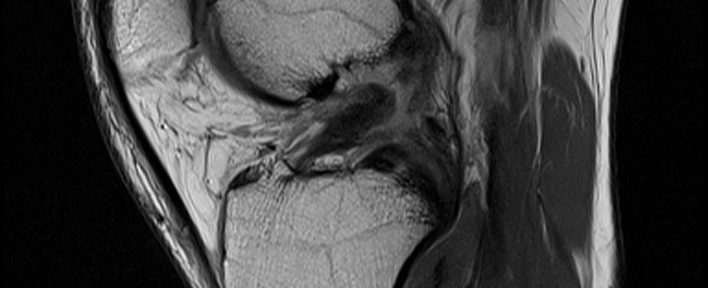

ACL Tear Natural Healing Case Report #50Case 50 | Natural Healing of Complete ACL Rupture: From Severe Ihara Type IV to Perfect Regeneration (ACLOAS Grade 0)